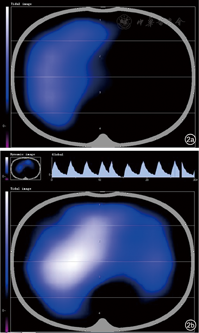

有研究试图确定使用这些气道廓清技术是否可以改善患者氧合、呼吸力学、肺功能,并减少机械通气时间、ICU住院时间、再入院或急诊次数、感染频率,提高生活质量等。一项儿科受试者的回顾性队列研究[96]评估了烧伤患者采用机械通气治疗时肝素和NAC的使用效果,结果表明,5000 U雾化肝素与3 ml 20% NAC交替使用,在最初的7 d内可减少小儿烧伤患者再次插管、呼吸机使用时间和死亡率。通过影像学变化也可判断治疗的效果,如气管镜吸痰治疗前后肺不张的改善情况(图1)。电阻抗断层成像(electrical impedance tomography,EIT)是以生物电阻为基础的功能成像技术,胸EIT借助微电压在胸内气体产生微电流,积分测算肺内气体随呼吸电阻值变化动态、立体成像,可以在气道廓清治疗过程中及前后比较治疗效果(图2)。

气道廓清主要包括患者评估、方案制定、方案执行和监测、回顾、记录4个步骤,每日应当对患者重新评估,以不断优化气道廓清方案(图3、图4)。患者评估需要包括患者基本病史、一般情况、功能评定(肺通气功能、咳嗽相关肌肉功能等)、需求评估(痰液黏度和量)和禁忌证评估等,机械通气患者还应当考虑患者呼吸支持水平、氧合情况、氧储备功能等。方案制定必须基于患者评估,同时建议包含痰液松动技术和咳嗽及相关技术以达到更好的痰液廓清效果,若痰液黏度较高,建议加强痰液水合或使用祛痰药物以促进痰液清除。